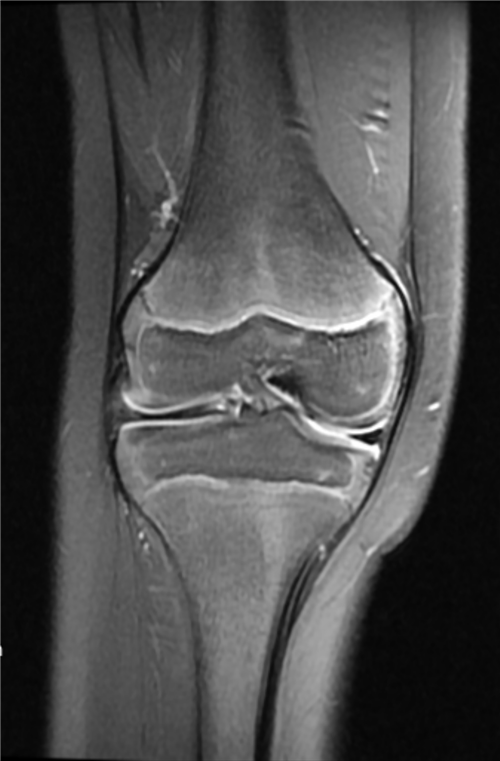

盘状半月板核磁表现

半月板是位于膝关节内侧和外侧的软骨结构,起到减震和稳定关节的作用。盘状半月板是指半月板的形态异常,较正常的半月板大而厚,尤其是在体部呈盘状。盘状半月板可能会受到损伤,例如撕裂、破裂或移位,导致疼痛、肿胀和关节功能受限。